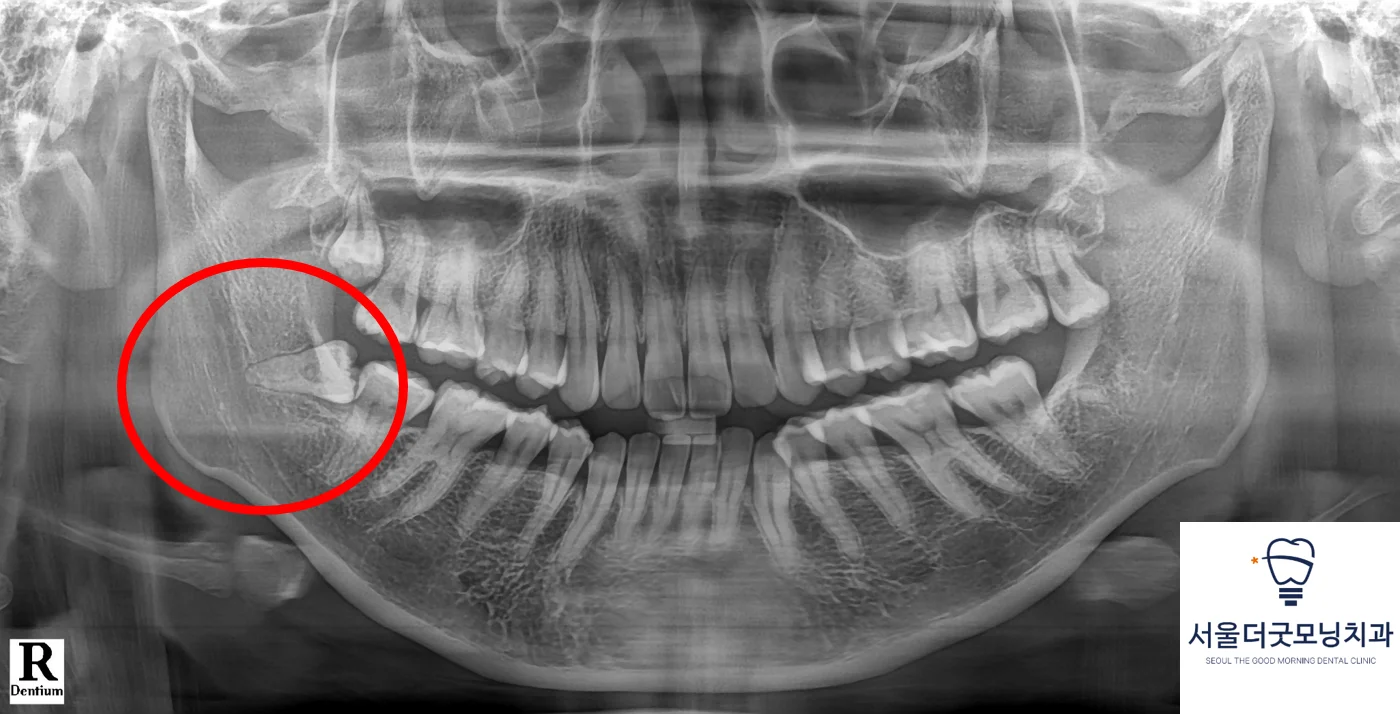

1️⃣ 파노라마 X-ray에서 보이는 매복사랑니

📌 설명 이미지 (파노라마)

• 사랑니의 기울기 확인

• 앞 어금니와의 충돌 여부

• 신경관과의 대략적 거리 판단

서울더굿모닝치과 광명사거리에서는

매복사랑니 진단 시 기본적으로 파노라마 촬영을 시행합니다.

다만, 파노라마만으로는 신경과의 정확한 거리 판단이 어렵습니다.